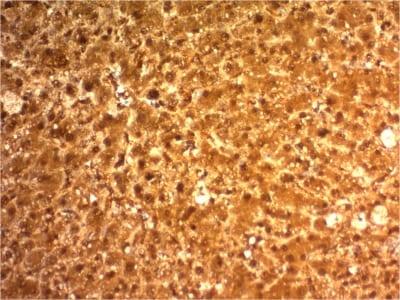

Positive Control

293Tcells. Hepatocellular Carcinoma (HCC).

IHC, FFPE (verified)

IHC (FFPE) (verified)

Higher concentration may be required for direct detection using primary antibody conjugates than for indirect detection with secondary antibody|Immunohistology (formalin): 2-4 ug/mL for 30 minutes at RT|Staining of formalin-fixed tissues requires boiling tissue sections in 10 mM citrate buffer, pH 6.0, for 10-20 minutes followed by cooling at RT for 20 minutes|Optimal dilution for a specific application should be determined by user